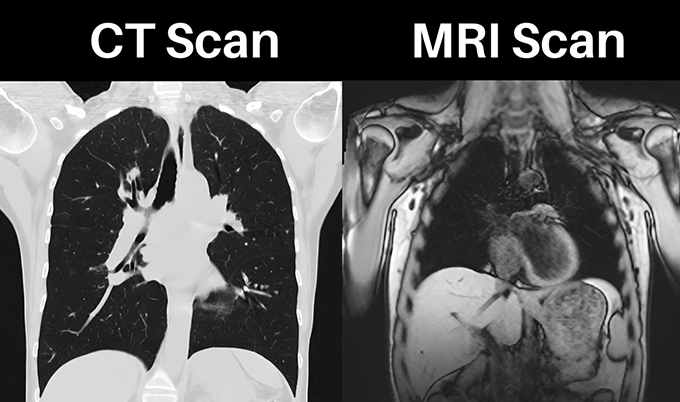

CT scans aren’t the first choice for diagnosing simple gallstones, but they play an important role in specific situations. The sensitivity of CT for detecting gallstones sits around 75% – lower than ultrasound – because many stones don’t show up clearly on CT images. But CT excels at evaluating complications from gallstone disease and identifying other conditions that might be causing your symptoms.

The detection rate depends entirely on stone composition. Only 15-20% of gallstones contain enough calcium to be “radiopaque” – visible on CT scans. These calcified stones appear bright white and are easy to spot. The remaining 80-85% of gallstones are made primarily of cholesterol or bilirubin. On CT, cholesterol stones may appear darker than the surrounding bile (hypoattenuating) or exactly the same density as bile (isodense). When stones match bile density, they’re essentially invisible on CT.

The scan itself takes just 5-10 minutes. You lie on a table that slides into a large donut-shaped machine. The CT scanner rotates around you, taking multiple X-ray images from different angles. A computer processes these images into detailed cross-sectional views. For gallbladder evaluation, contrast dye is often given through an IV to help visualize blood flow and inflammation. The contrast makes inflamed tissues light up, clearly showing areas affected by infection or inflammation.